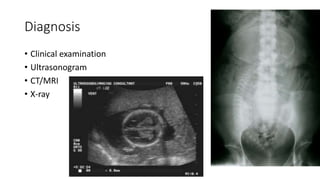

Diagnosis

• Clinical examination

• Ultrasonogram

• CT/MRI

• X-ray